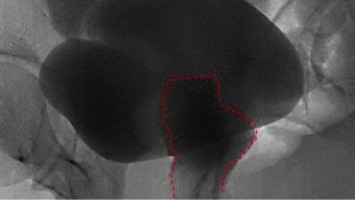

Urogenitale Fistel: So wurde die Patientin endlich beschwerdefrei

Eine 36-Jährige hat bereits mehrere abdominale Operationen hinter sich, um die bestehende Endometriose zu behandeln. Die daraus bedingte Urogenitalfistel und damit einhergehende totale Harninkontinenz konnten bislang nicht erfolgreich behandelt werden.